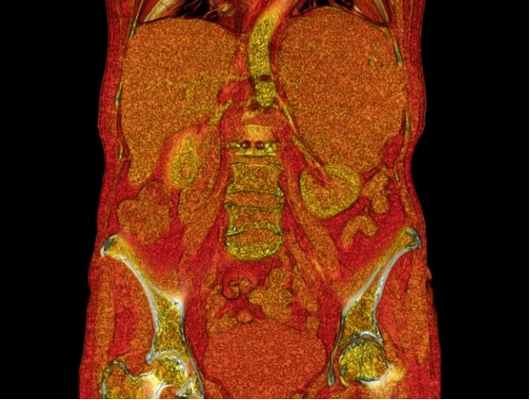

В настоящее время широко используется УЗИ, КТ или МР-томография для выявления расположения опухоли надпочечника, наличия метастазов.

Для обнаружения первичной опухоли, оценки поражения лимфатических узлов, выявления метастазов назначают ультразвуковое исследование почек и надпочечников, других органов, КТ или МРТ с контрастом, рентгенографию органов грудной клетки, сцинтиграфию.

При подозрении на рак надпочечников для исключения метастазов опухоли проводятся компьютерная томография легких и брюшной полости, магнитно-резонансная томография головного мозга. Исследуется компьютерный фенотип опухоли. Цитоплазма клеток аденом и миелолипом надпочечника характеризуется высоким содержанием липидов в отличие от зрелых опухолей. Это свойство используется при денситометрии опухоли. Оценивается плотность жировых и нежировых структур в неконтрастную фазу. Нативная плотность образования менее 10 HU характерна для доброкачественных аденом, альдостером, липом, кист, гематом, абсцессов. Повышение плотности более 10 HU возможно при адренокортикальном раке, феохромоцитоме, метастазах, нейрогенных опухолях, лимфомах. При исследовании плотности на разных фазах выведения контрастного вещества аденомы быстро снижают показатели плотности, злокачественные опухоли имеют тенденцию к задержке контрастного вещества. Разделительная точка – вымывание 50% контраста за 10 минут.